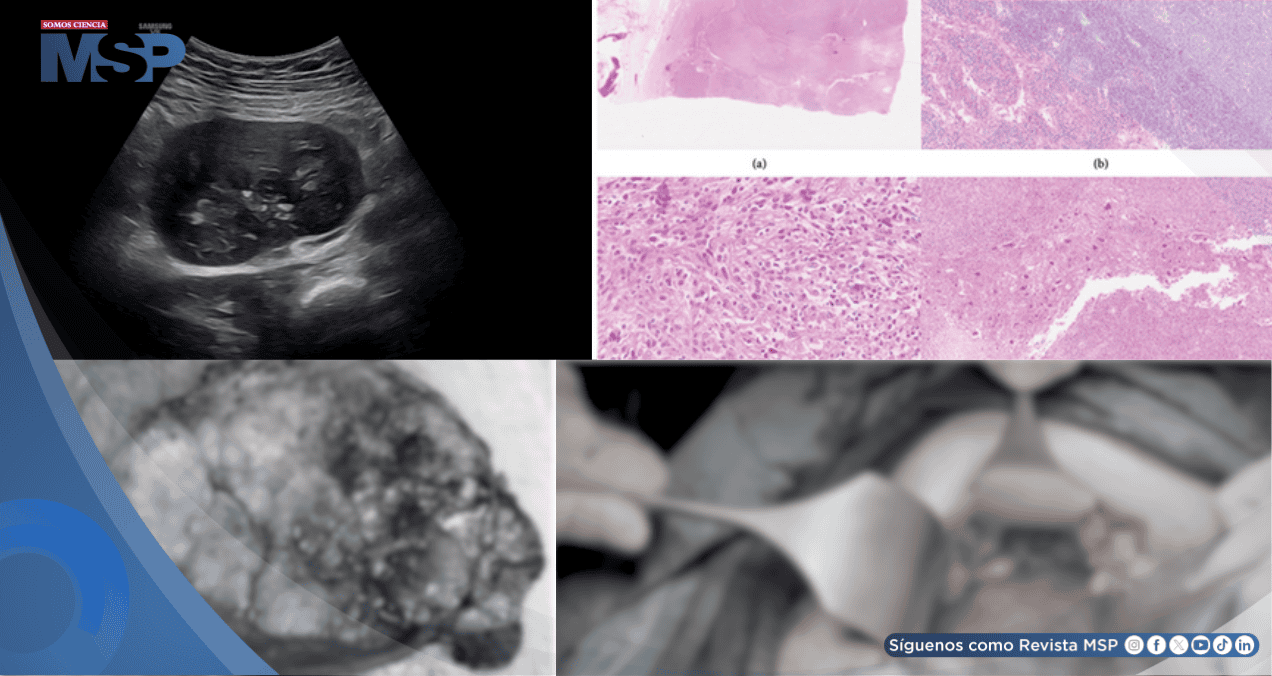

Durante la ecografía, se identificó de manera incidental una masa sólida de aproximadamente 8 x 7 cm en la región anexial derecha. Esta lesión presentaba bordes irregulares y calcificación central, características que inicialmente sugirieron un tumor mesenquimal sólido.

La exploración intraoperatoria reveló que tanto los ovarios como las trompas de Falopio eran normales. Sin embargo, se identificó una masa sólida semimóvil de aproximadamente 10 cm localizada en el retroperitoneo, adyacente al lóbulo inferior del hígado, que se extendía de derecha a izquierda cruzando la línea media.

Veintisiete días después del parto, la paciente fue intervenida por el equipo de cirugía general para la resección completa de la masa. La pieza quirúrgica medía 13 x 8 x 7.5 cm, presentaba una superficie multilobulada, color blanco sucio y áreas de hemorragia y necrosis focal. El examen microscópico reveló un tumor bien circunscrito y lobulado.

La evaluación histológica mostró dos componentes principales. Por un lado, se identificó una Enfermedad de Castleman de tipo hialino-vascular, caracterizada por centros germinales penetrados por vasos sanguíneos hialinizados, creando la típica apariencia de "piruleta".

Por otro lado, el componente neoplásico consistía en células fusiformes a epitelioides dispuestas en patrones fasciculares y verticilados, con núcleos irregulares, cromatina vesicular y nucléolos prominentes.

Se observaron además células gigantes multinucleadas atípicas, un denso infiltrado inflamatorio y una actividad mitótica elevada (8-19 mitosis por 10 campos de alta resolución) con presencia de necrosis.

El estudio inmunohistoquímico fue determinante para el diagnóstico definitivo. Las células tumorales mostraron positividad para marcadores específicos del linaje de células dendríticas foliculares: CD21, D2-40 (podoplanina) y clusterina.

El índice de proliferación Ki-67 fue del 30-35%. Otros marcadores, incluyendo citoqueratina, S100, CD34 en células tumorales, y EBV (EBER), resultaron negativos.

El examen integral confirmó el diagnóstico de Sarcoma de Células Dendríticas Foliculares (FDCS) asociado a Enfermedad de Castleman de tipo hialino-vascular.